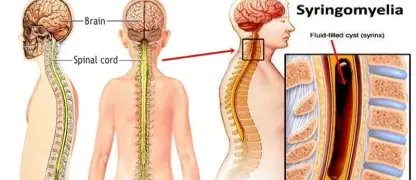

Visualizing concepts related to CTE